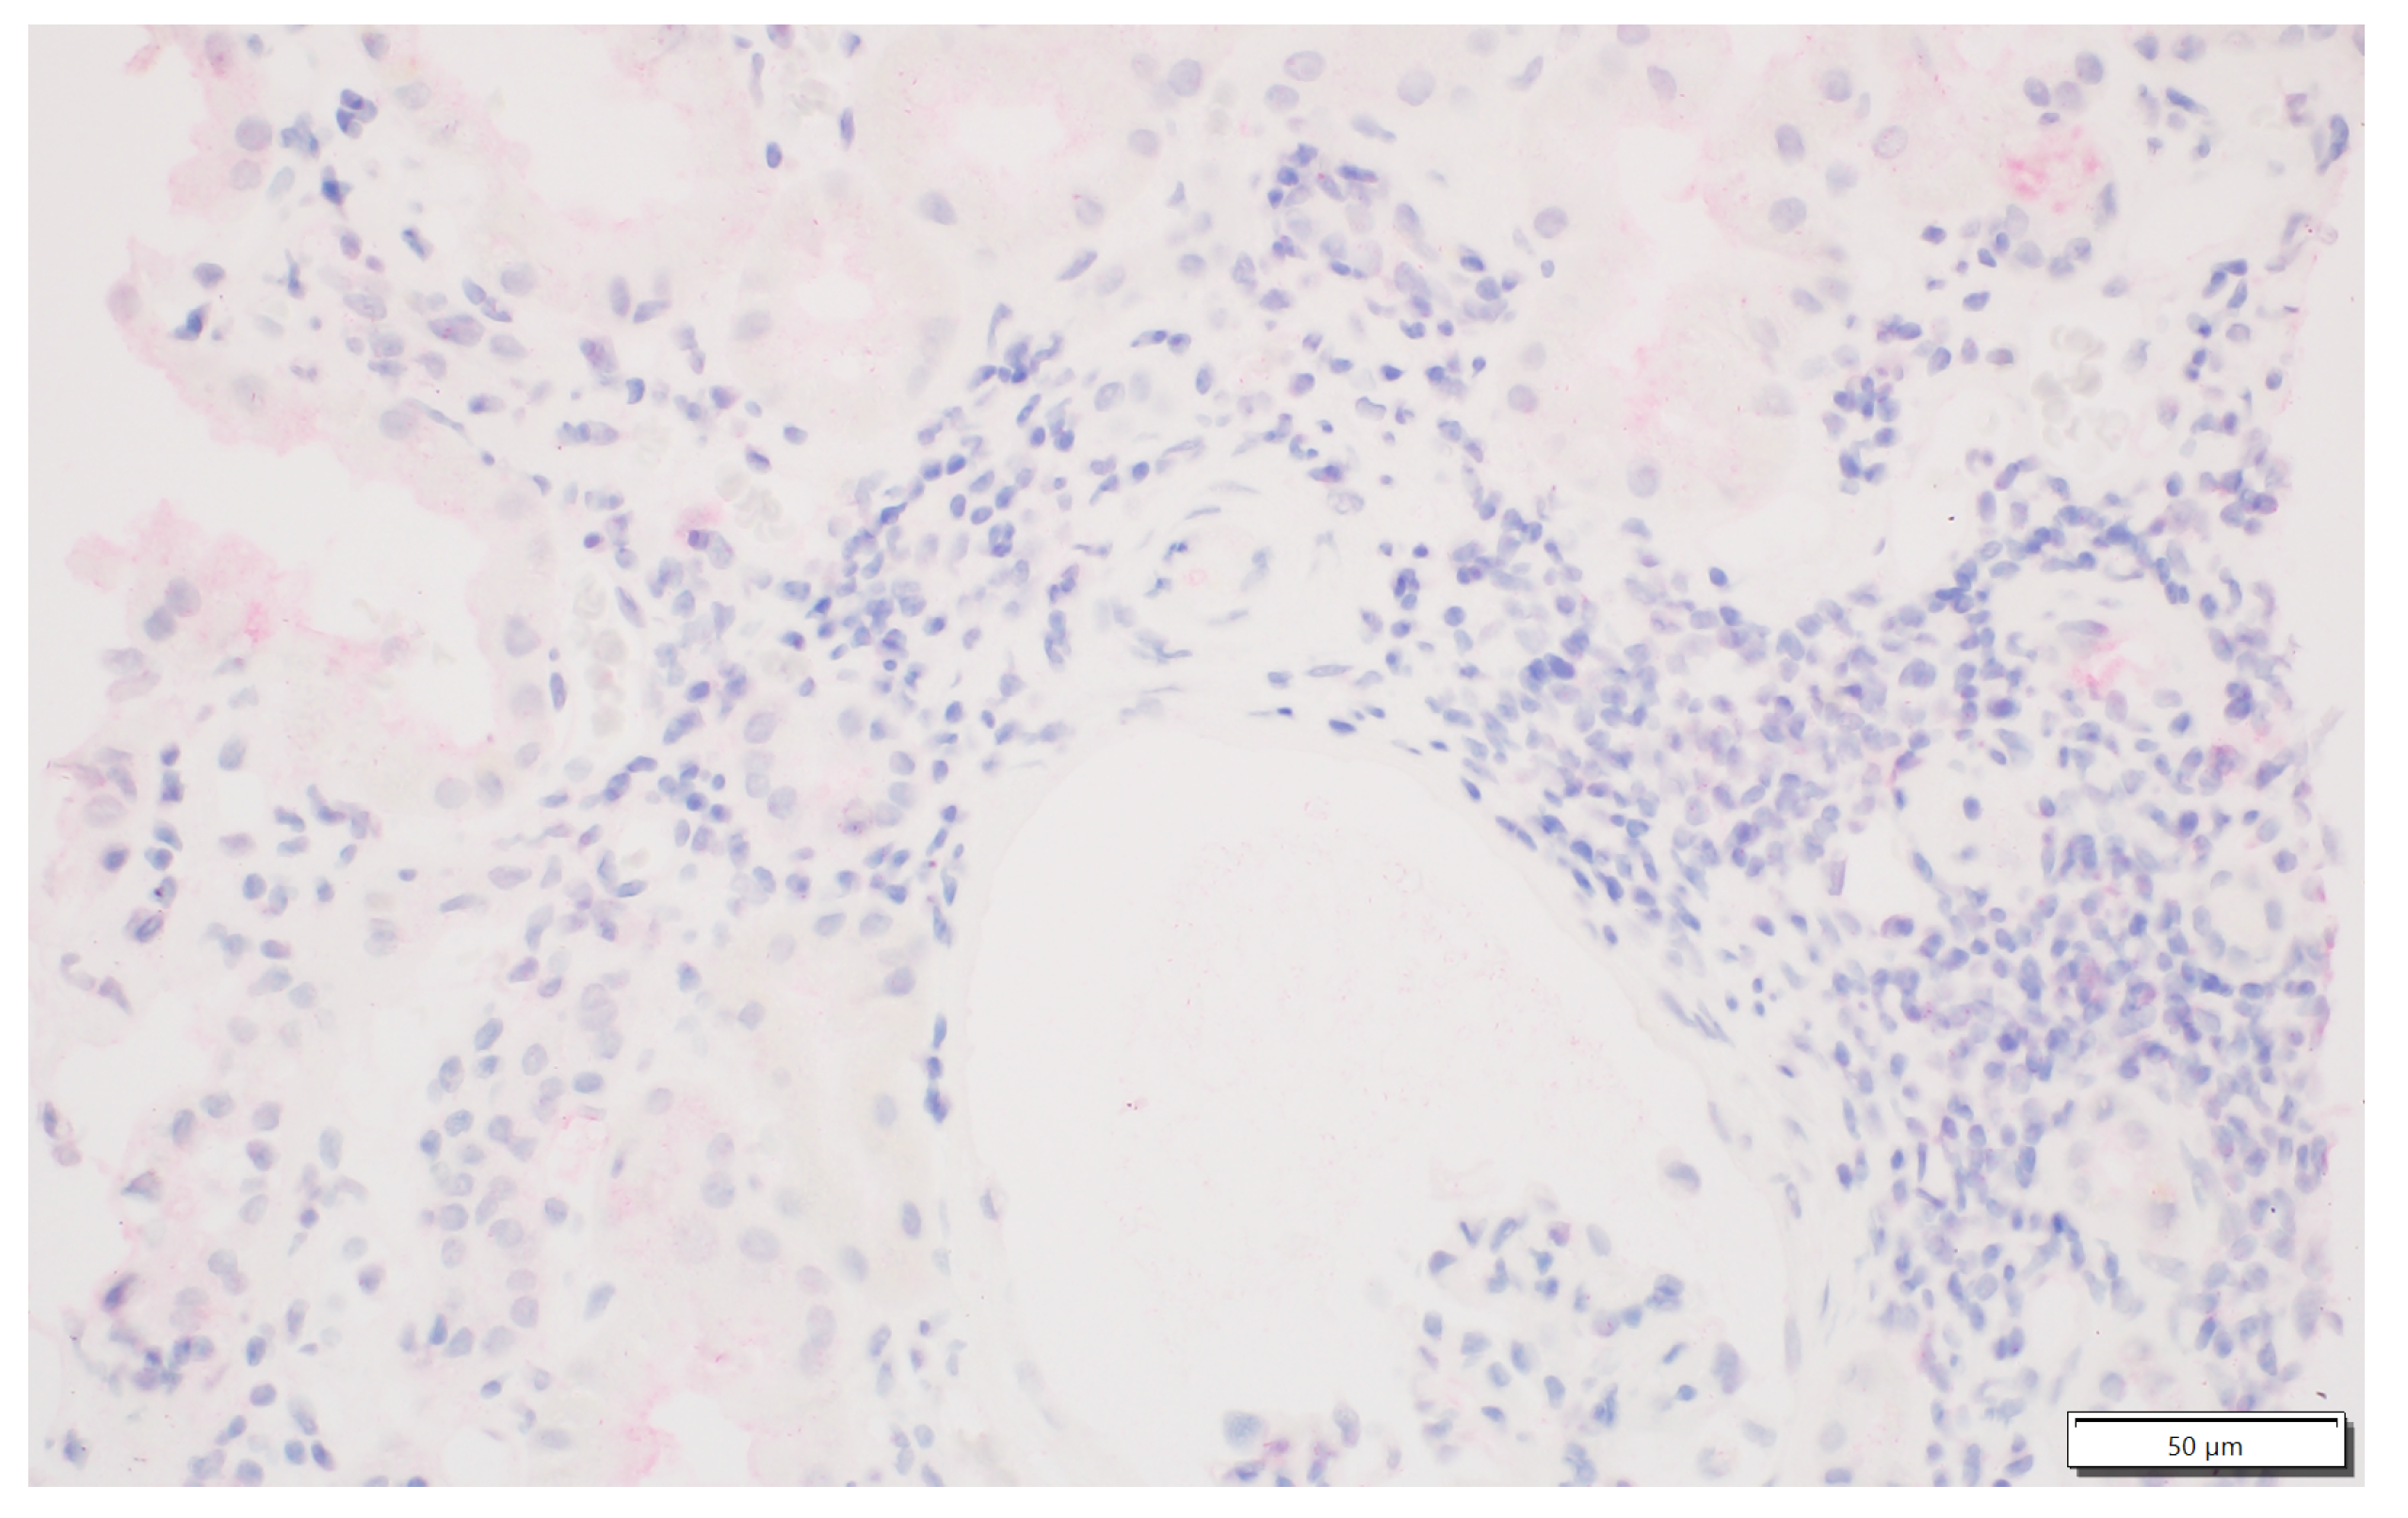

2.2. IDO1 Expression Analysis

3.2. Rejection Observed in Patients Displaying IDO1 Expression in Interstitial Foci

3.3. Analysis of Antibody-Mediated Rejection (AMR)

3.4. T-Cell-Mediated Rejection (TCMR) Analysis

3.5. Pure Types of Rejection